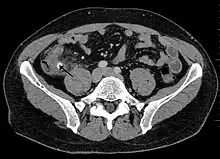

Computed tomography

Where it is readily available, computed tomography (CT) has become frequently used, especially in people whose diagnosis is not obvious on history and physical examination. Although some concerns about interpretation are identified, a 2019 Cochrane review found that sensitivity and specificity of CT for the diagnosis of acute appendicitis in adults was high.[59] Concerns about radiation tend to limit use of CT in pregnant women and children, especially with the increasingly widespread usage of MRI.[60][61]

The accurate diagnosis of appendicitis is multi-tiered, with the size of the appendix having the strongest positive predictive value, while indirect features can either increase or decrease sensitivity and specificity. A size of over 6 mm is both 95% sensitive and specific for appendicitis.[62]

However, because the appendix can be filled with fecal material, causing intraluminal distention, this criterion has shown limited utility in more recent meta-analyses.[63] This is as opposed to ultrasound, in which the wall of the appendix can be more easily distinguished from intraluminal feces. In such scenarios, ancillary features such as increased wall enhancement as compared to adjacent bowel and inflammation of the surrounding fat, or fat stranding, can be supportive of the diagnosis. However, their absence does not preclude it. In severe cases with perforation, an adjacent phlegmon or abscess can be seen. Dense fluid layering in the pelvis can also result, related to either pus or enteric spillage. When patients are thin or younger, the relative absence of fat can make the appendix and surrounding fat stranding difficult to see.[63]